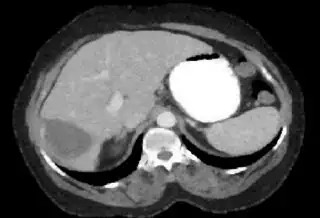

Below are some of the opened and segmented images. Of course there's more to be done in terms of

- separating out the liver region

- generalizing this to a large dataset

but hope this is at least a starting point.